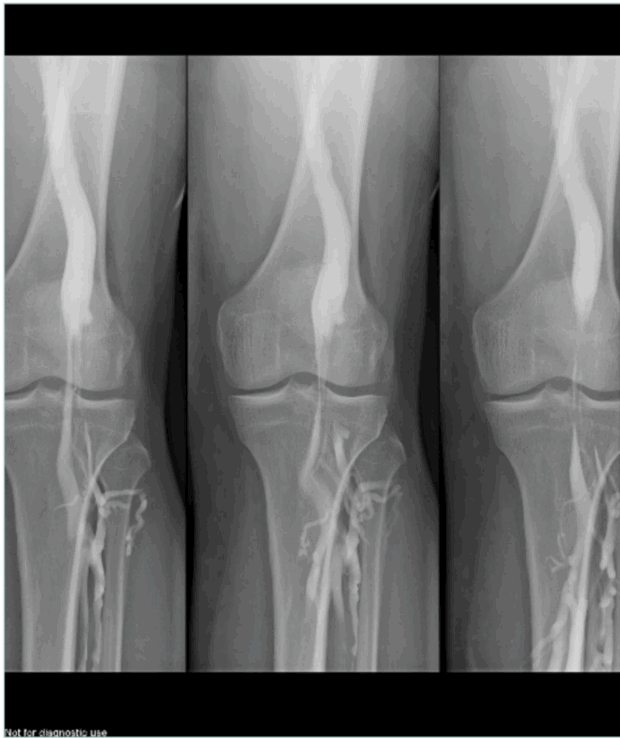

Our reference test remains dynamic phlebography.2 The examination is performed on a tilting table at 60° angle, with 3 manual injections of contrast agent: in neutral, foot extension, and foot flexion positions.

The surgeon should be in the room during the phlebography, for better evaluation of the anatomical pattern of the compression and to ask for more incidences as needed. In recurring varicose veins after small saphenous ablation, the surgeon can map the tributaries and perforators, which act as a spontaneous bypass over the compression (Figure 4 shows ascending phlebography: vein compression in the 3 positions of the foot; Figures 5 and 6 show ascending phlebography: spontaneous bypass of a venous popliteal compression).